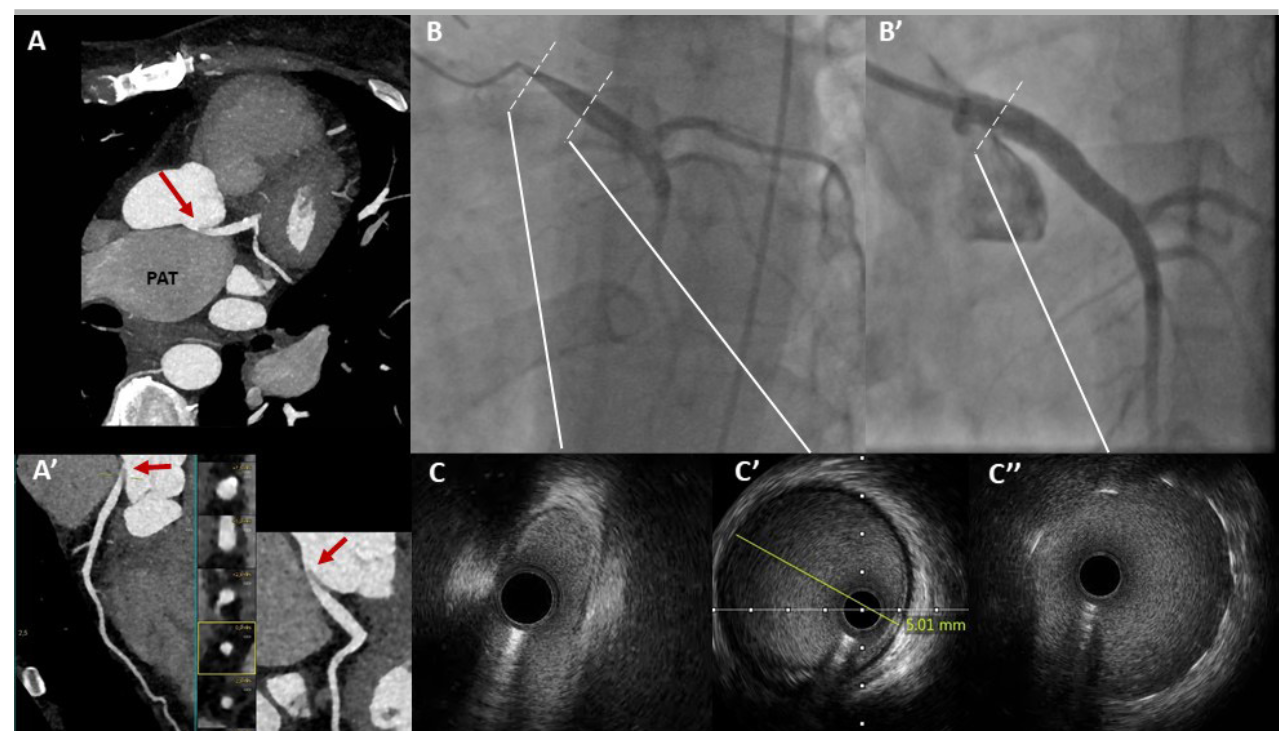

Coronary computed tomography angiography (CCTA) showed significant enlargement of the pulmonary artery trunk and right pulmonary artery with secondary external compression of the left main coronary artery (LMCA) causing severe ostial/proximal LMCA stenosis. Coronary angiography and evaluation with intravascular ultrasound (IVUS) confirmed severe ostial stenosis of the LMCA. Percutaneous coronary intervention (PCI) with implantation of a 4.0 x 15-mm drug-eluting stent, with good angiographic and IVUS result, was performed. At clinical follow-up, the angina pectoris symptoms had completely resolved.